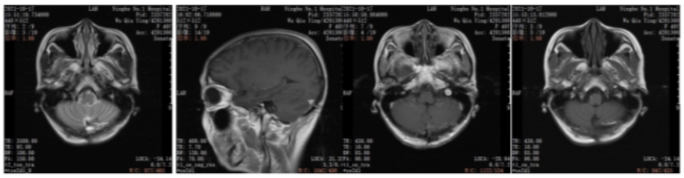

2021年6月颅脑增强MRI:左侧小脑占位,考虑转移瘤。

图2.颅脑增强MRI

2022年5月颅脑增强MRI:左侧小脑肿瘤切除术后改变。

疗效评价CR,继续维持曲妥珠单抗(汉曲优)+吡咯替尼+卡培他滨治疗方案

图3.颅脑增强MRI